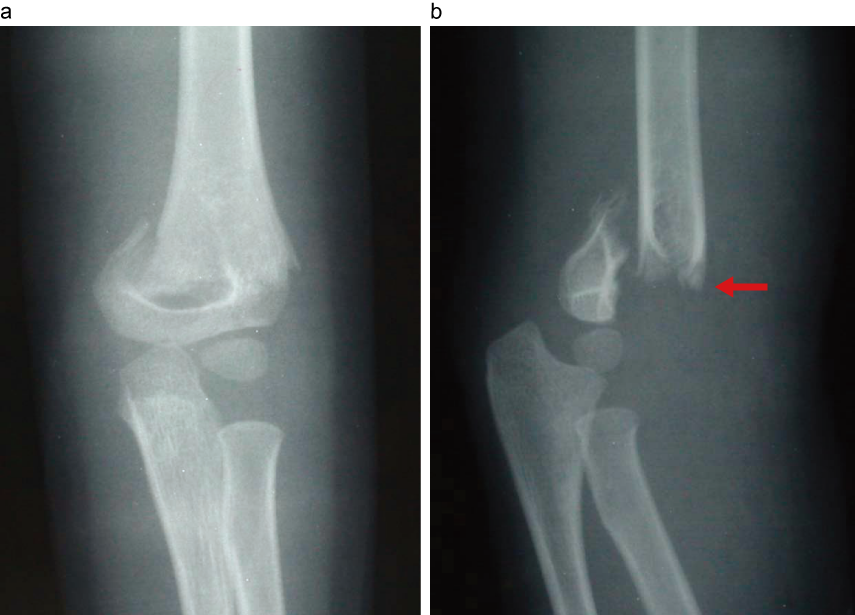

4歳男児 左上腕骨顆上骨折 机から転落して受傷

左上腕骨顆上骨折

a:正面像。遠位骨片は尺側に転位。

b:側面像。遠位骨片が背側に転位(伸展型)。

4歳男児 小児の骨折は、正確なX線写真撮影が困難で見逃しやすい。必ず正側2方向撮影を行う。疼痛のため通常の側面撮影は困難なため側面撮影の際はカセッテを体幹に挟み撮影するとよい。